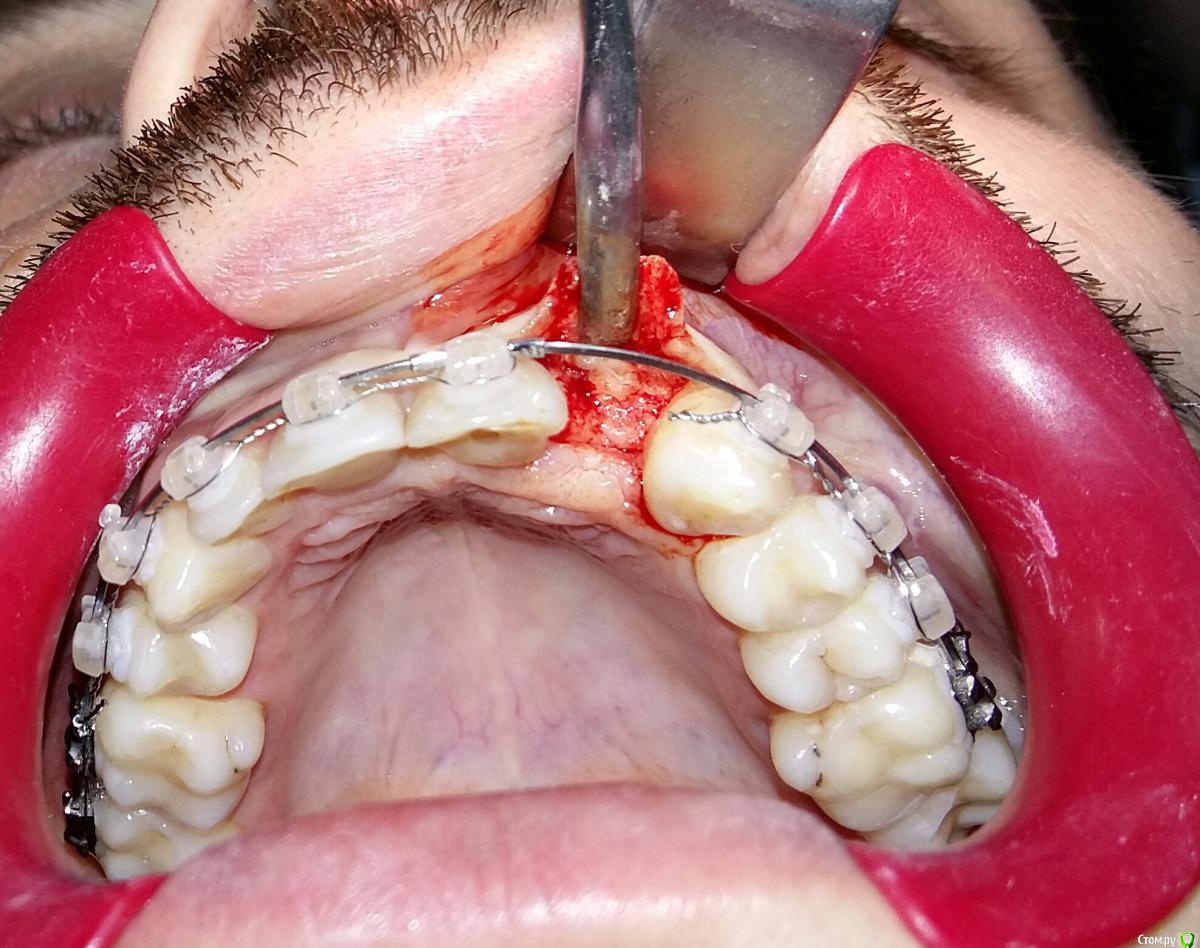

Kostoprav Опубликовано 8 июля, 2015 Поделиться Опубликовано 8 июля, 2015 ИЗНАЧАЛЬНАЯ СИТУАЦИЯ ПОЛУЧИЛОСЬ сори что нет фото до имплантации. Блок взял с тела челюсти, фиксировал двумя винтами (во время имплантации выкрутил только один), присыпал gen os, укрыл дермой-получил заметный прирост слизистой) имплант альфадент 3,75х11,5 2 Ссылка на комментарий

Kostoprav Опубликовано 8 июля, 2015 Автор Поделиться Опубликовано 8 июля, 2015 Видно что блок прирос. ЗдоровоОстальное оценить сложноМне нравится положение импланта в плане оси.Но уровень заглубления не ясенТакже не видно прироста десныВ общем мало данных для оценкиНо опять же вам именно она и нужна?по вестибюлярной поверхности заглубил приблизительно на 1мм с небной больше получилось. слизистая по сравнению с первым разом значительно толще стала, доказать к сожалению не могу так как не делал фото(: я выложил этот пост не только ради оценки, может кому из начинающих данный случай сгодиться 3 Ссылка на комментарий

Kostoprav Опубликовано 28 июля, 2015 Автор Поделиться Опубликовано 28 июля, 2015 Сколько времени прошло после фиксации блока? Чем забирает е блок? на момент имплантации 6 мес. забор блока делал линденманом Ссылка на комментарий